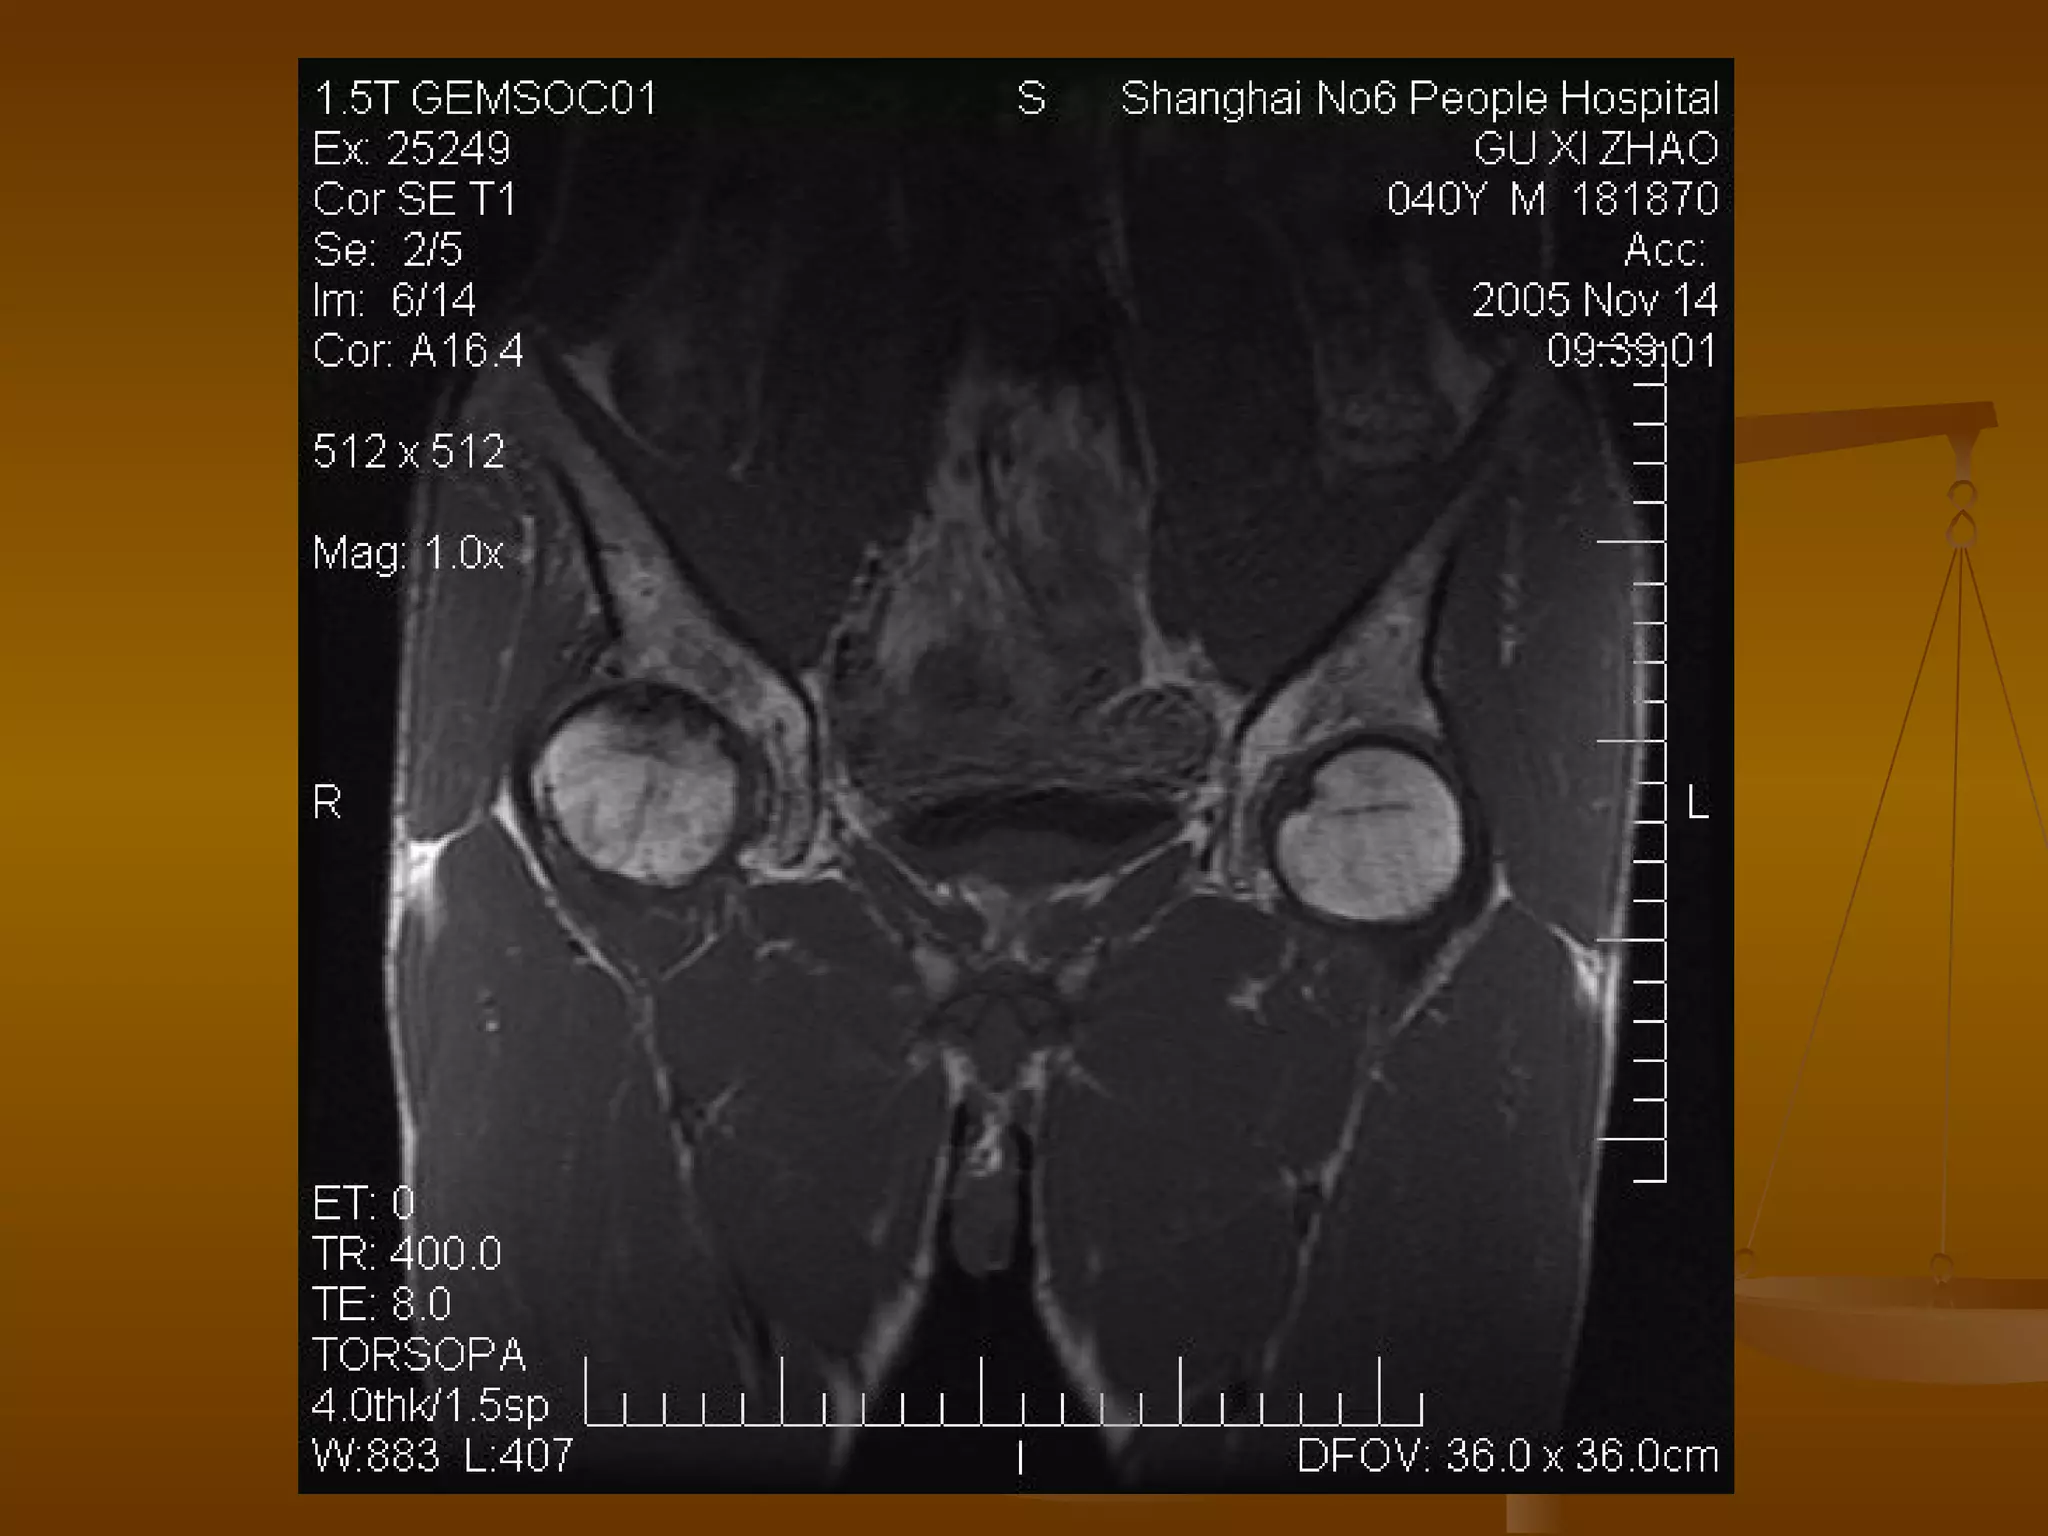

MRI 诊断 正常成人股骨头的 MRI 表现 正常成人股骨头骨髓内富含脂肪,在 T1 及 T2 加权图像上成圆形的高信号。 股骨头及股骨颈表面骨皮质均为低信号。 在冠状面上,股骨头中央的承重骨小梁,表现为自外下缘到内上缘的稍低信号带。 闭合的骨骺线为横行低信号线,两端与致密骨相连。

MRI 诊断   Ⅰ 期 髋关节间隙正常,股骨头光整、不变形。 典型的 MRI 表现为股骨头前上部负重区在 T1W 上显示线样低信号区, T2W 上显示为局限性信号升高或“双线征”。 在 MRI 上出现“双线征”,这是股骨头缺血坏死的特异性 MRI 表现之一。

MRI 诊断   Ⅱ期 髋关节间隙正常,股骨头光整、不变形。 在 T1W 上,股骨头前上部负重区,有硬化缘围绕较低、不均匀信号的新月形坏死区。 在 T2W 上,病灶为星月形高信号区。 在 X 线平片上,股骨头负重区内可见高密度的硬化区,内可伴有小囊样改变。